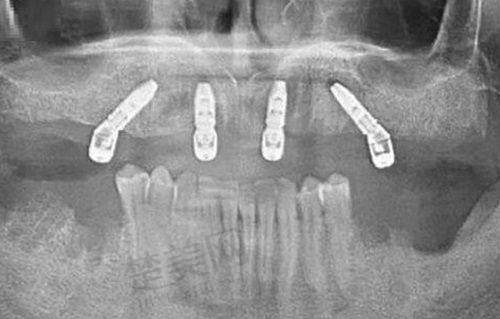

匠心口腔门诊部设有拔牙补牙、牙齿矫正等项目。拔牙补牙是常见的口腔治疗项目,对于牙齿出现问题的患者来说,及时的拔牙或补牙能避免问题进一步恶化。该门诊部在这方面有一定的技术保护,能让患者在相对舒适的状态下完成治疗。